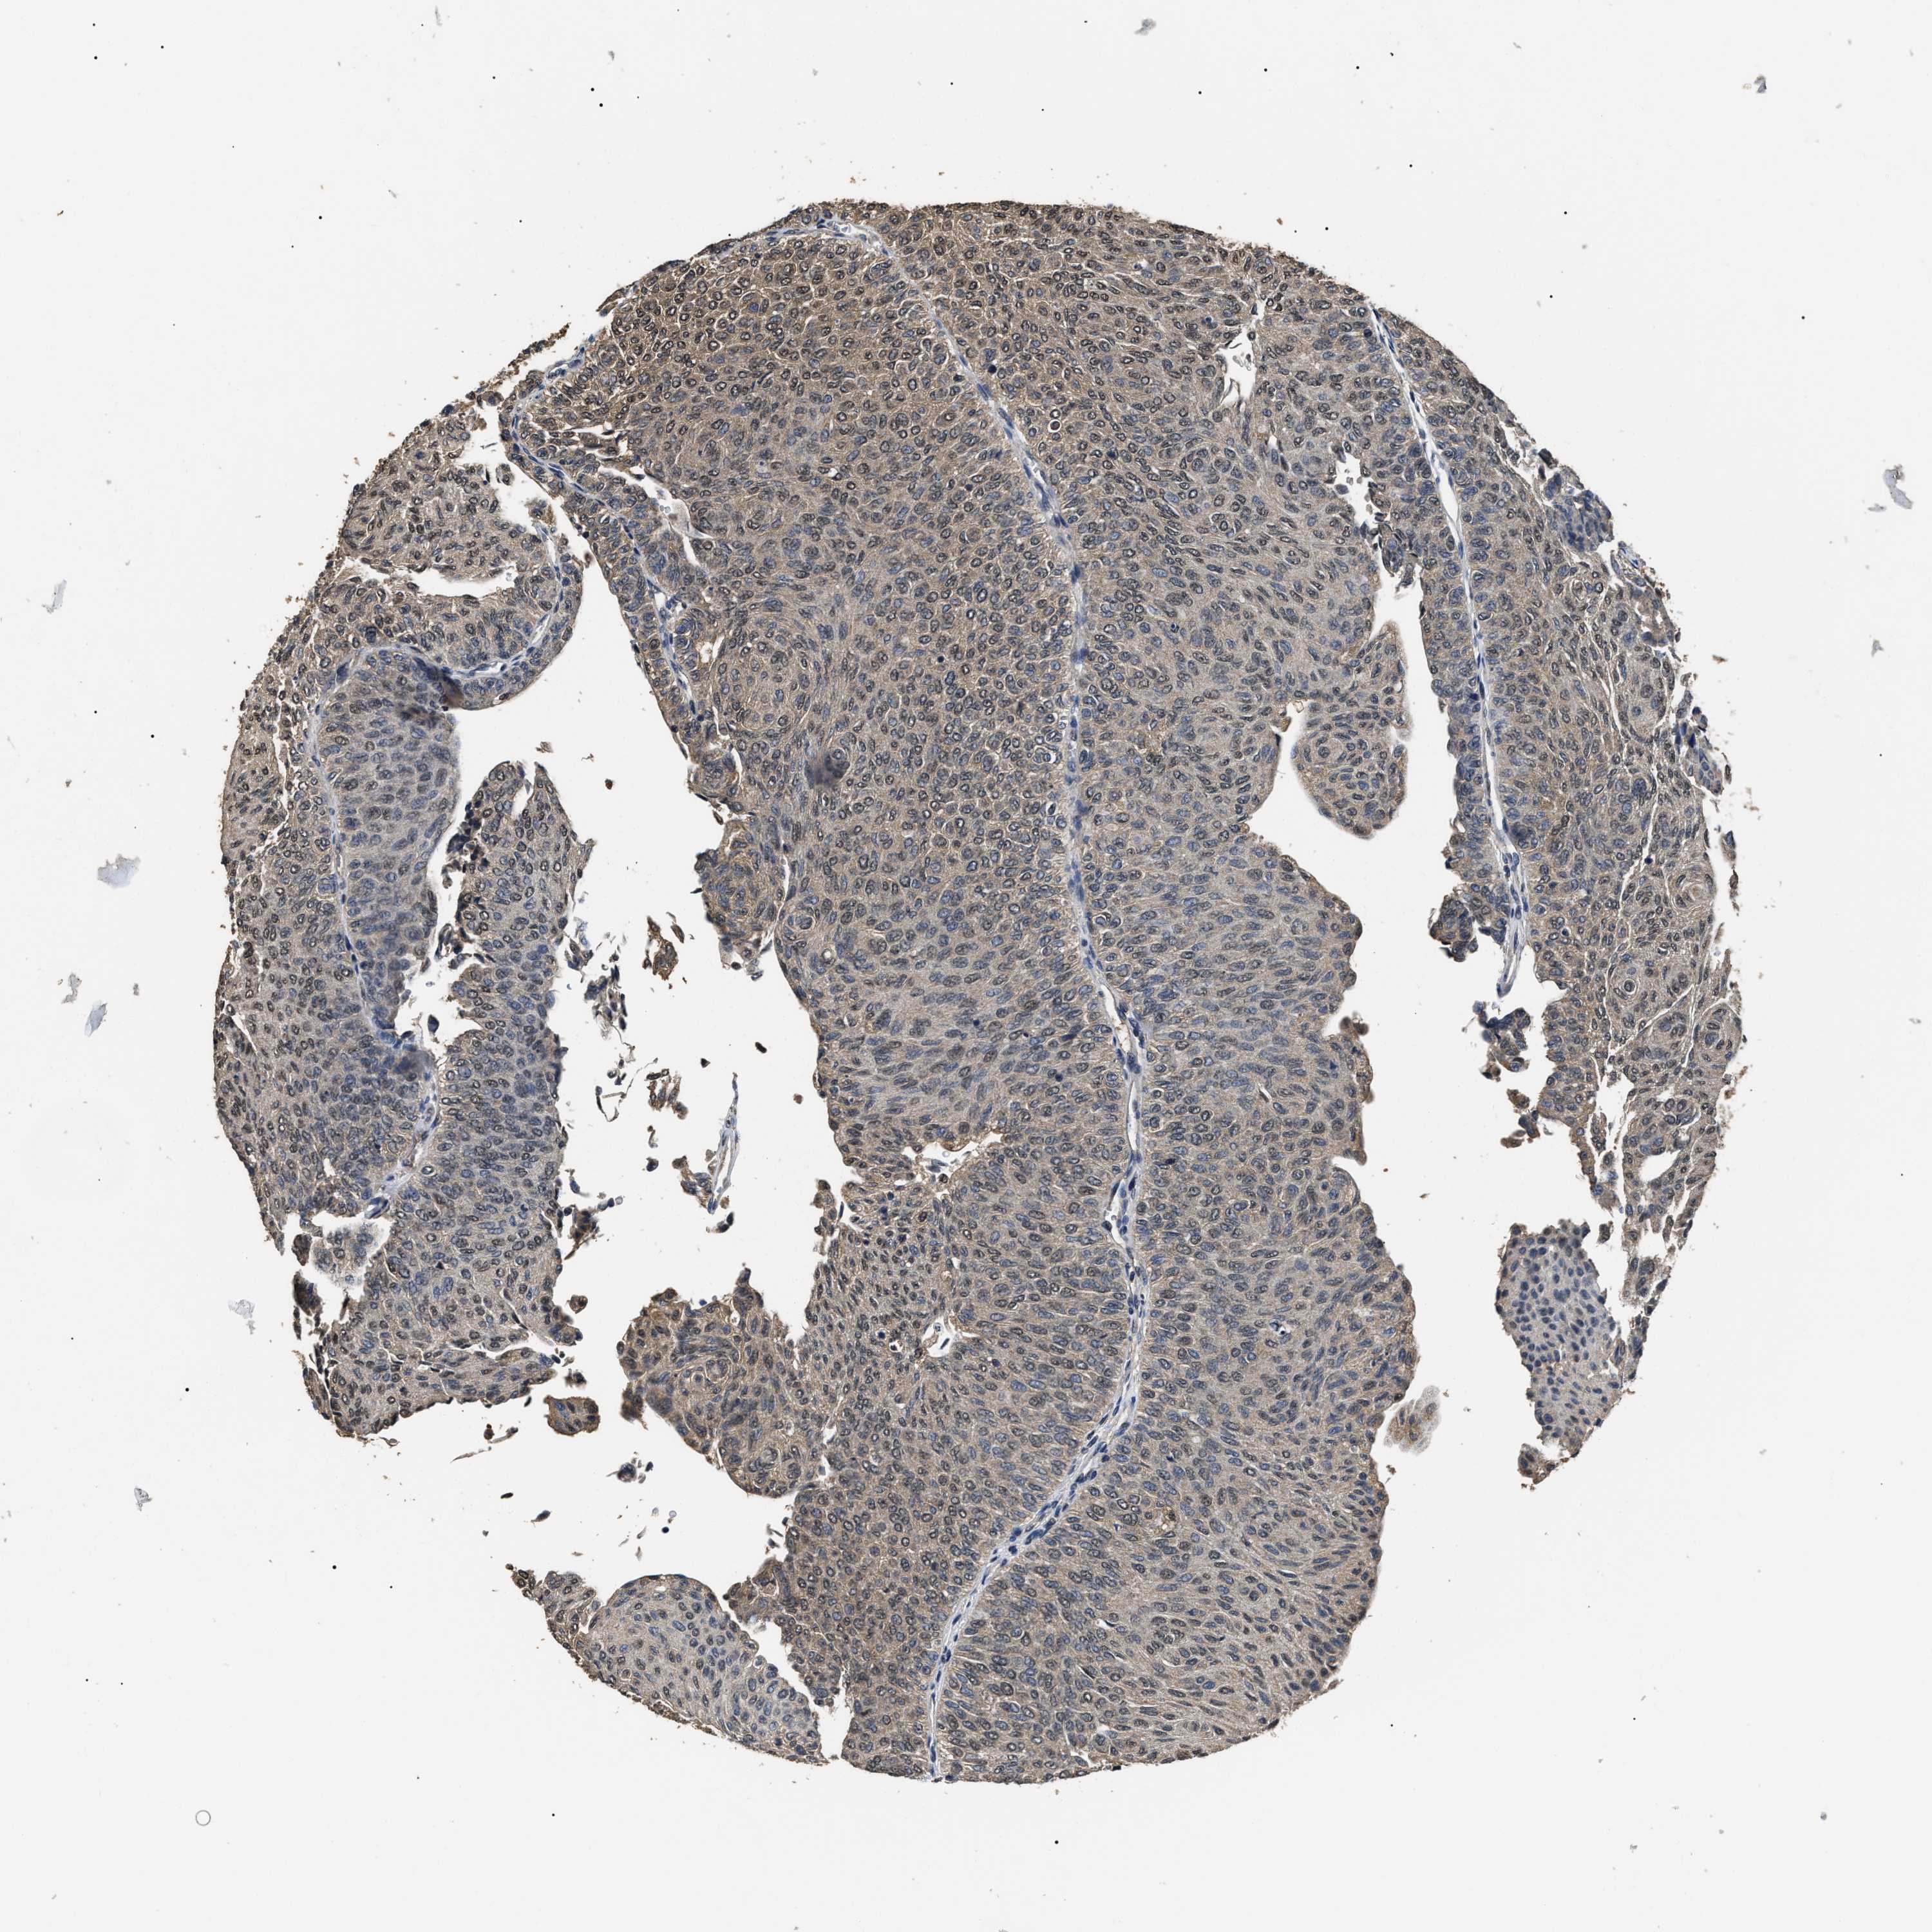

UROTHELIAL CANCER - Protein expressioni

A mouse-over function shows sample information and annotation data. Click on an image to view it in a full screen mode. Samples can be filtered based on level of antibody staining by selecting one or several of the following categories: high, medium, low and not detected. The assay and annotation is described here.

Note that samples used for immunohistochemistry by the Human Protein Atlas do not correspond to samples in the TCGA dataset.

Antibody stainingi

Antibody staining in the annotated cell types in the current human tissue is reported as not detected, low, medium, or high, based on conventional immunohistochemistry profiling in selected tissues. This score is based on the combination of the staining intensity and fraction of stained cells.

Each image is clickable and will lead to virtual microscopy that enables deeper exploration of all samples and also displays staining intensity scores, fraction scores and subcellular localization as well as patient and tissue information for each sample.

Antibody HPA006702

Antibody CAB021101

Urothelial carcinoma, Low grade

Urothelial carcinoma, High grade